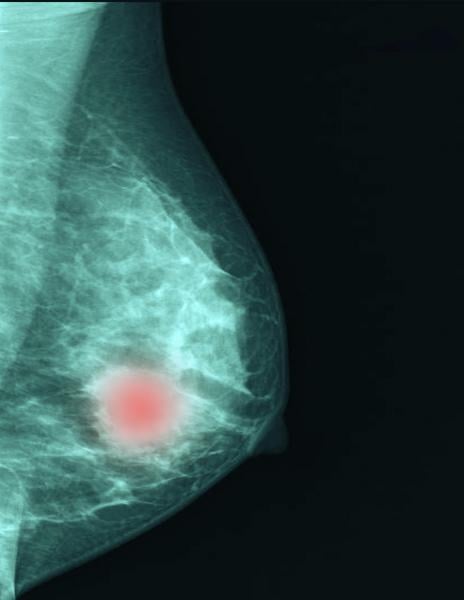

July 29, 2025 — A new technology that harnesses AI to analyze mammograms and improve the accuracy of predicting a woman’s personalized five-year risk of developing breast cancer has received Breakthrough Device designation from the Food and Drug Administration (FDA).

Headlines around the world the past several months declared that artificial intelligence (AI) is better at detecting ...